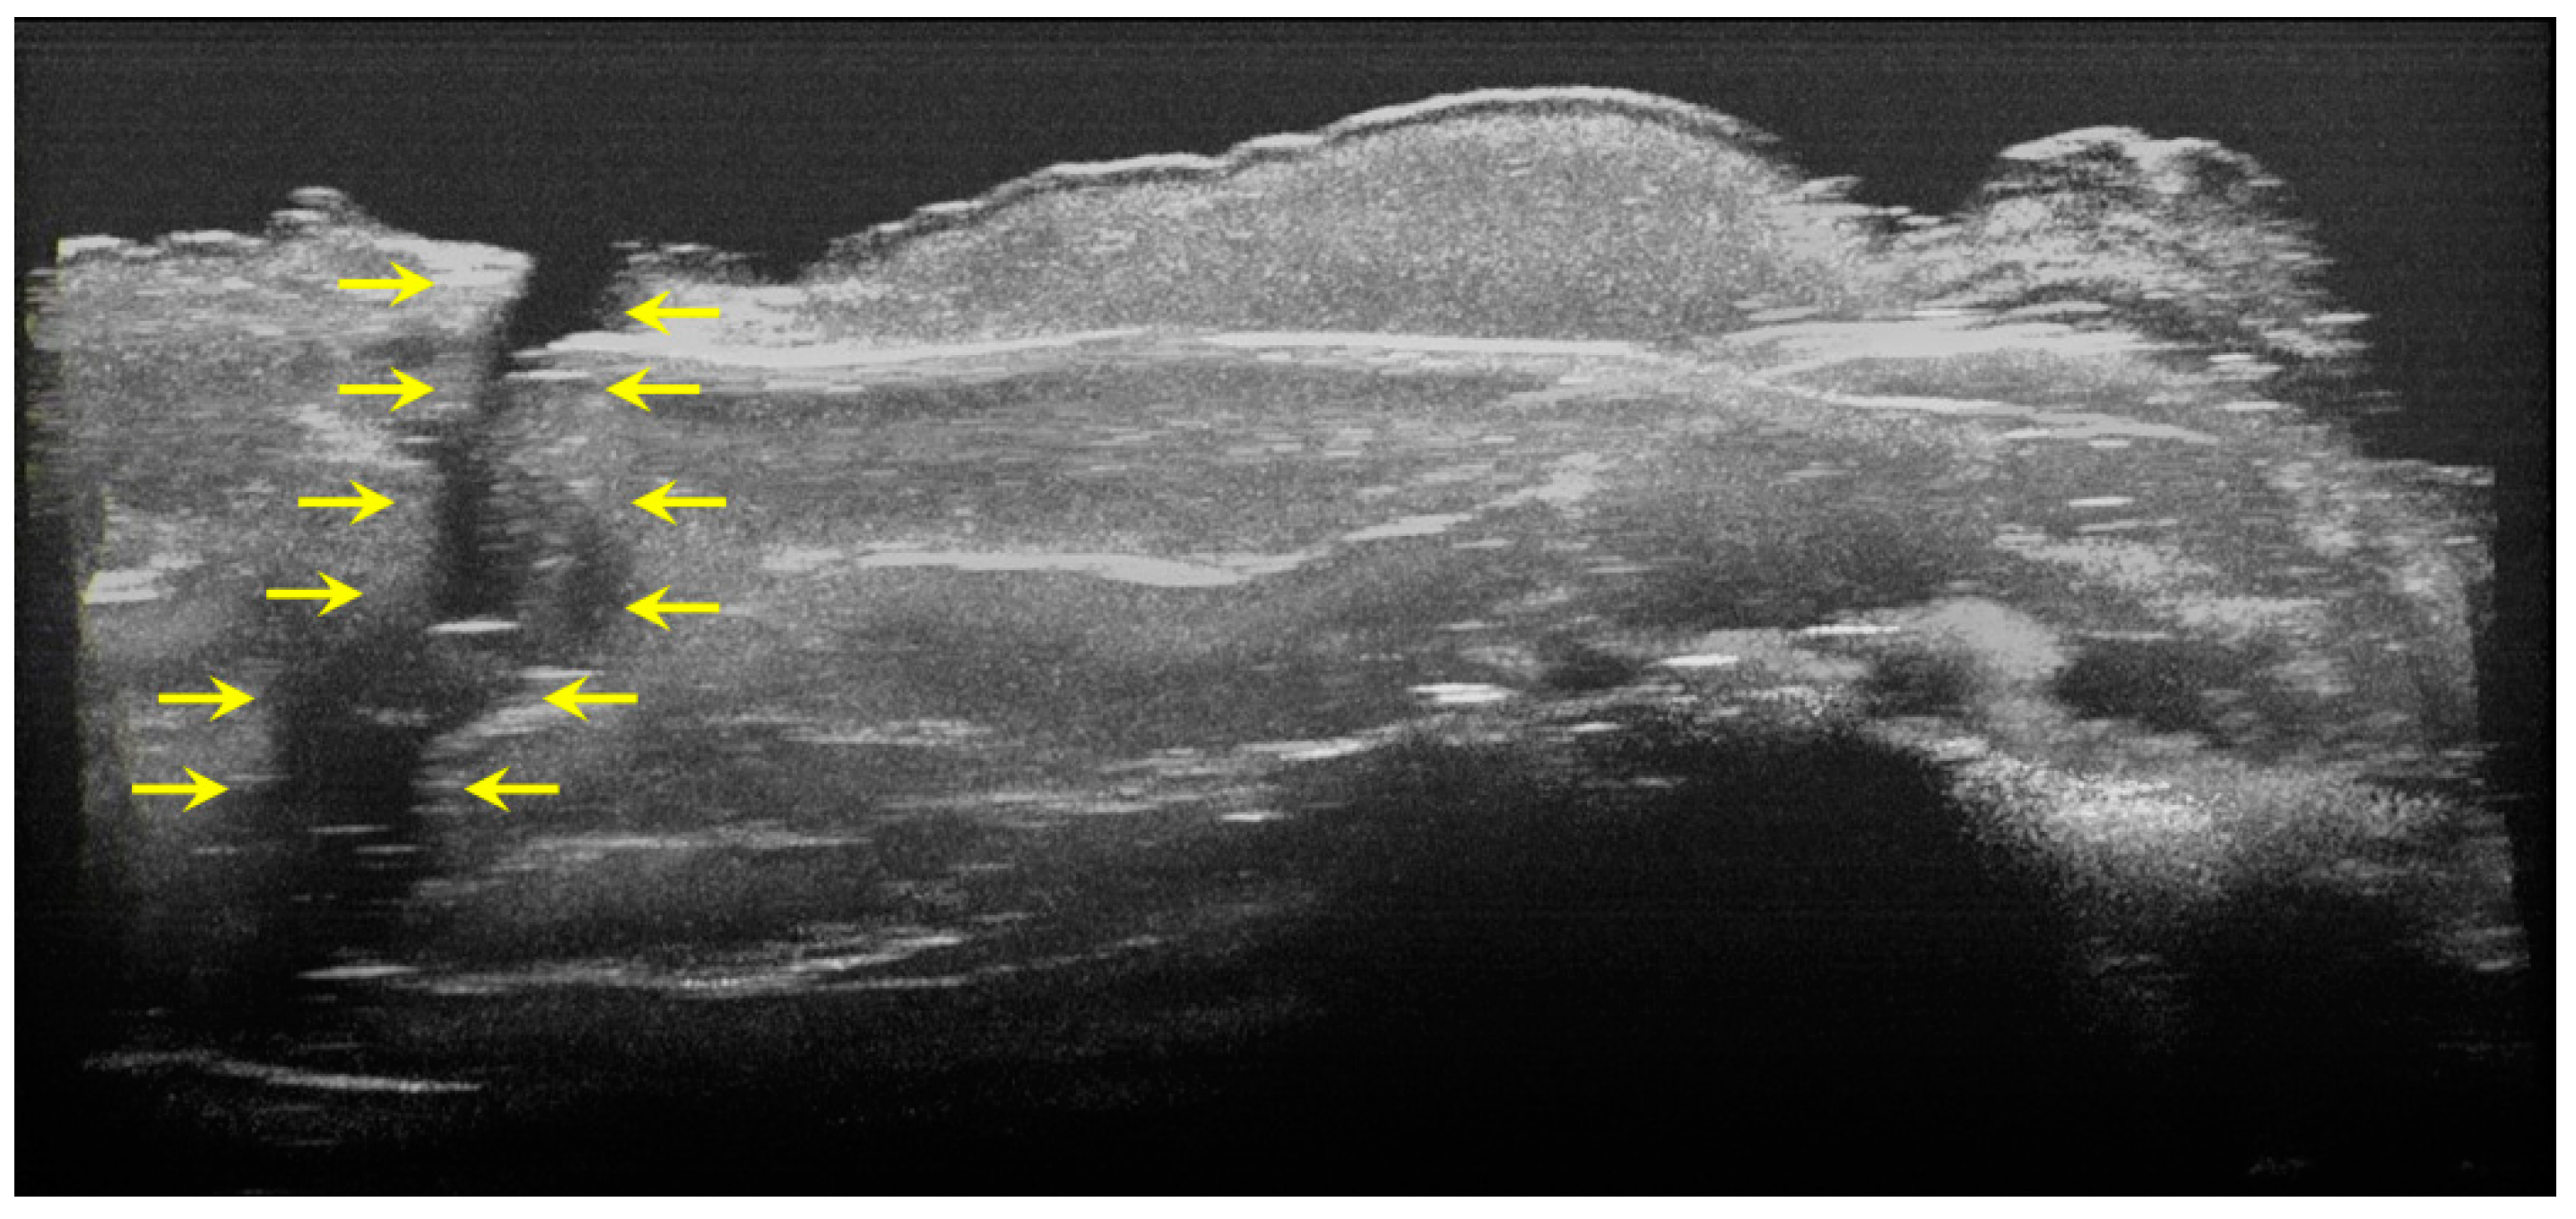

During the OCT examination of enamel defects, the hypomineralization was characterized by an intense, inhomogeneous OCT signal. In those areas, the enamel was demineralized; therefore, the image was diffuse (Figure 4).

Figure 4.

Two-dimensional OCT images of a tooth with hypomineralization (areas marked by yellow arrows): (a) cusp presenting a hypomineralization area; (b) extended area of hypomineralization, divided by a bridge of healthy enamel; (c) small-size hypomineralization area; (d) cusp presenting a hypomineralization area (scale bar 100 μm).